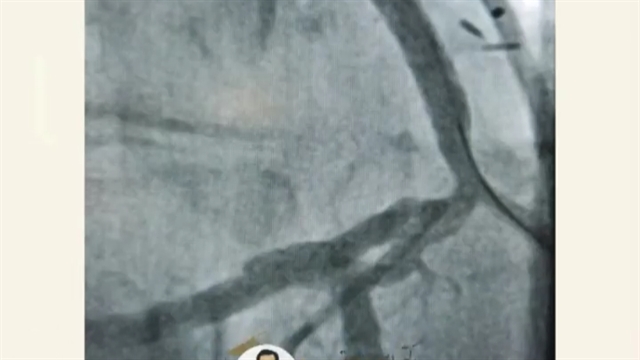

آنژیوپلاستی پس از جراحی قلب باز